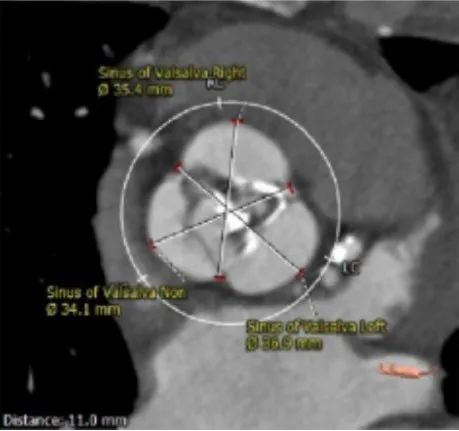

主动脉根部测量:

ANNULUS

SOV DIAMETER

LVOT

STJ

ASCENDING AORTA

LEFT VENTRICLE

冠脉高度测量:

LEFT CORONARY

左冠开口高度16.0mm

RIGHT CORONARY

右冠开口高度17.0mm

钙化分布

HU542钙化积分1364mm³